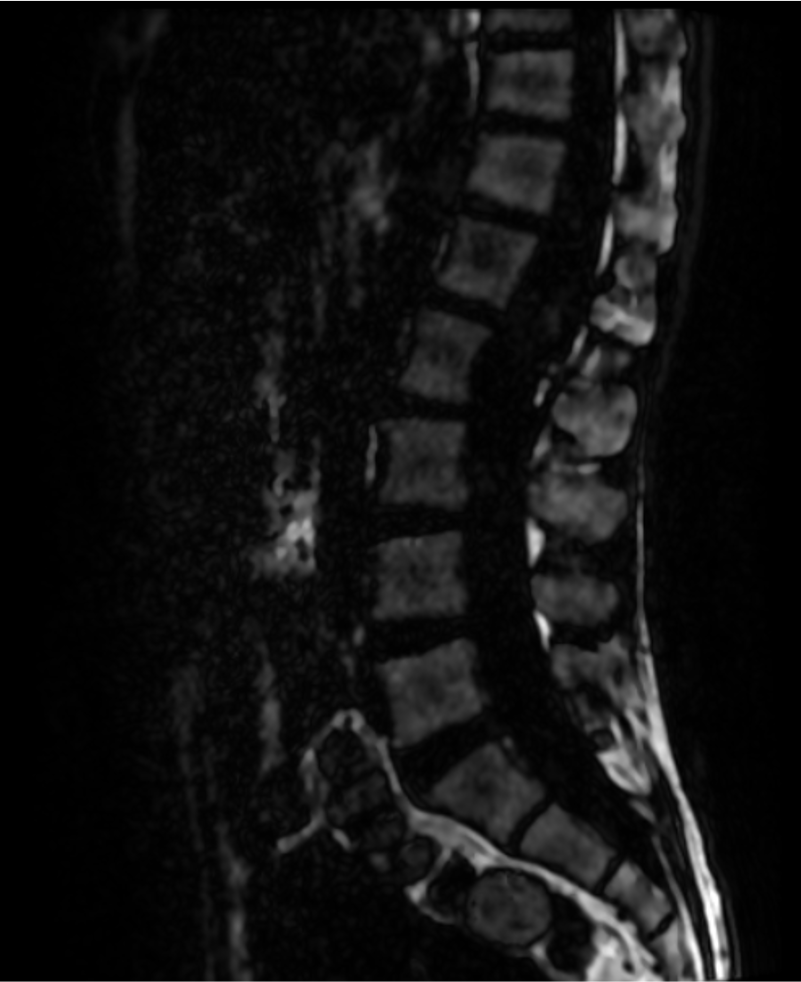

AXIAL T2

MRI is the modality of choice for evaluation of spinal epidermoid cysts. Although classically described as T1 hypointense, T2 hyperintense lesions with diffusion restriction, imaging appearances may be variable, particularly in chronic or protein-rich lesions.

In the present case, the lesion demonstrates T1 hyperintensity and T2 hypointensity, an atypical appearance attributed to dense keratinaceous debris, cholesterol crystals, high protein concentration, and chronic desiccation, resulting in shortening of T1 and T2 relaxation times. Such lesions are described as atypical or “white” epidermoid cysts.

While diffusion restriction is a characteristic feature, its absence does not exclude the diagnosis, especially in long-standing lesions with compact internal contents and in the setting of technical limitations of spinal diffusion imaging.